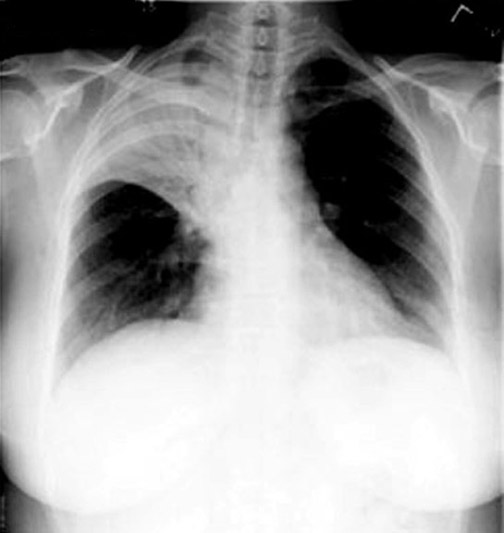

RUL Consolidation

- Lobar density: There is opacity in the projection of the right upper lung field corresponding to RUL. It is a triangular density.

- Consolidation extends to pleura and transverse fissure. Note that consolidation does not cross transverse fissure.

- Air bronchogram: You can see the air filled bronchi coursing through the density.

- The trachea is in midline and the transverse fissure is in its normal location (slightly retracted upwards), indicating that there is no significant loss of lung volume.